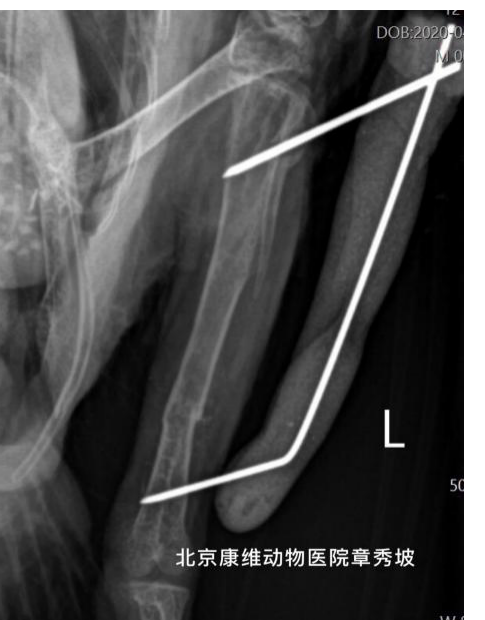

侧位x光片 该鹦鹉左后肢胫骨中后端横向骨折

术后第2周拆胫骨内钢针的x光片

术后周4拆除髓内针x光片